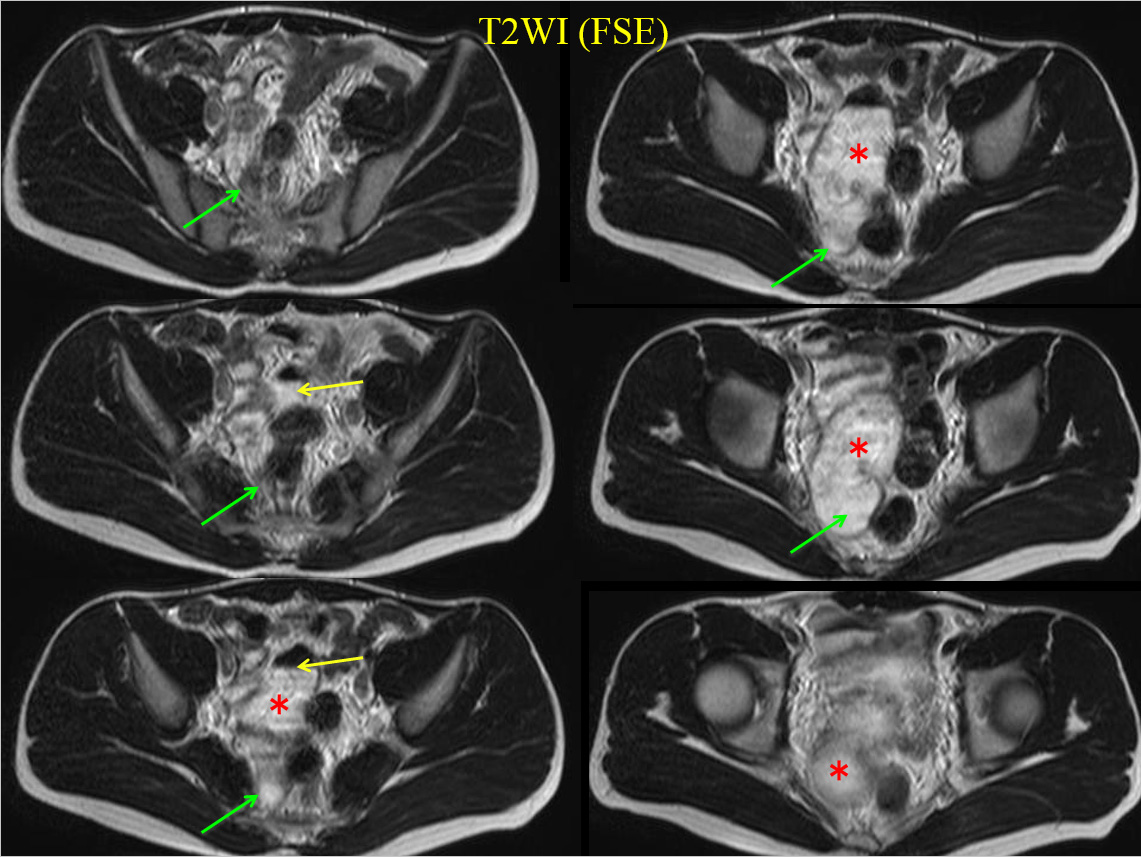

• T2WI (FSE)

MRでは、骨盤内に大きな嚢胞性病変を認める。

すなわちT2WI、T1WIでいずれも高進号を呈すが、脂肪抑制で抑制されず、造影で辺縁部のみわずかに濃染される。

内部には不均一で貯留物があると認識されるが、血性を示唆する所見には乏しい。

骨盤内の嚢胞性病変の鑑別となるが、男性であるため卵巣由来は否定的である。水平断像および冠状断像を丹念に読影すると、同病変は小腸と連続しており、腸管構造の一部であることがわかる。病変の局在は回腸末端に近く、年齢、経過を加味すると、メッケル憩室が最も考えられる。